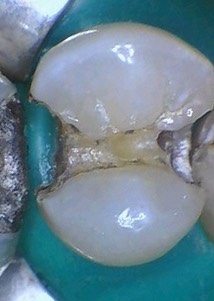

Mendel Sato #12 amalgam removal